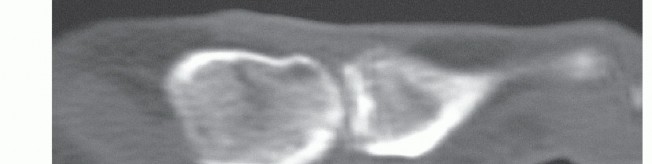

One 3-mm stab incision is done distal to the fractured sesamoid bone and distal to the weight-bearing area of the first MTP joint (TECH FIG 2B).

The guidewire (1.5-mm wire for 2.4-mm self-tapping Bold screws [Newdeal, Lyon, France]) is introduced under fluoroscopic control from the distal pole, perpendicular to the fracture line and subchondral to the sesamoid joint line (TECH FIG 2C).

- TECH FIG 2 • A. Fixation of the hallux in hyperextension. Compress the sesamoid against the metatarsal head to level the fracture fragments against the joint line. B. Place the stab incision distal to the sesamoid outside the weight-bearing area of the MTP joint. C. Place the guidewire perpendicular to the fracture line, subchondral from proximal to distal. D. The guidewire should just pierce the proximal cortex. The second guidewire is advanced to the distal cortex for exact measurement. (continued)

The length of the headless cannulated compression screw is measured as the difference to a second guidewire that is held next to the first and is advanced to the sesamoid cortex. The usual range is between 12 and 16 mm. The shortest screw available is 10 mm (Bold screws; TECH FIG 2D,E).

The screw should pierce the proximal cortex to enhance stability (TECH FIG 2F). The stab incision is closed with sterile strips.